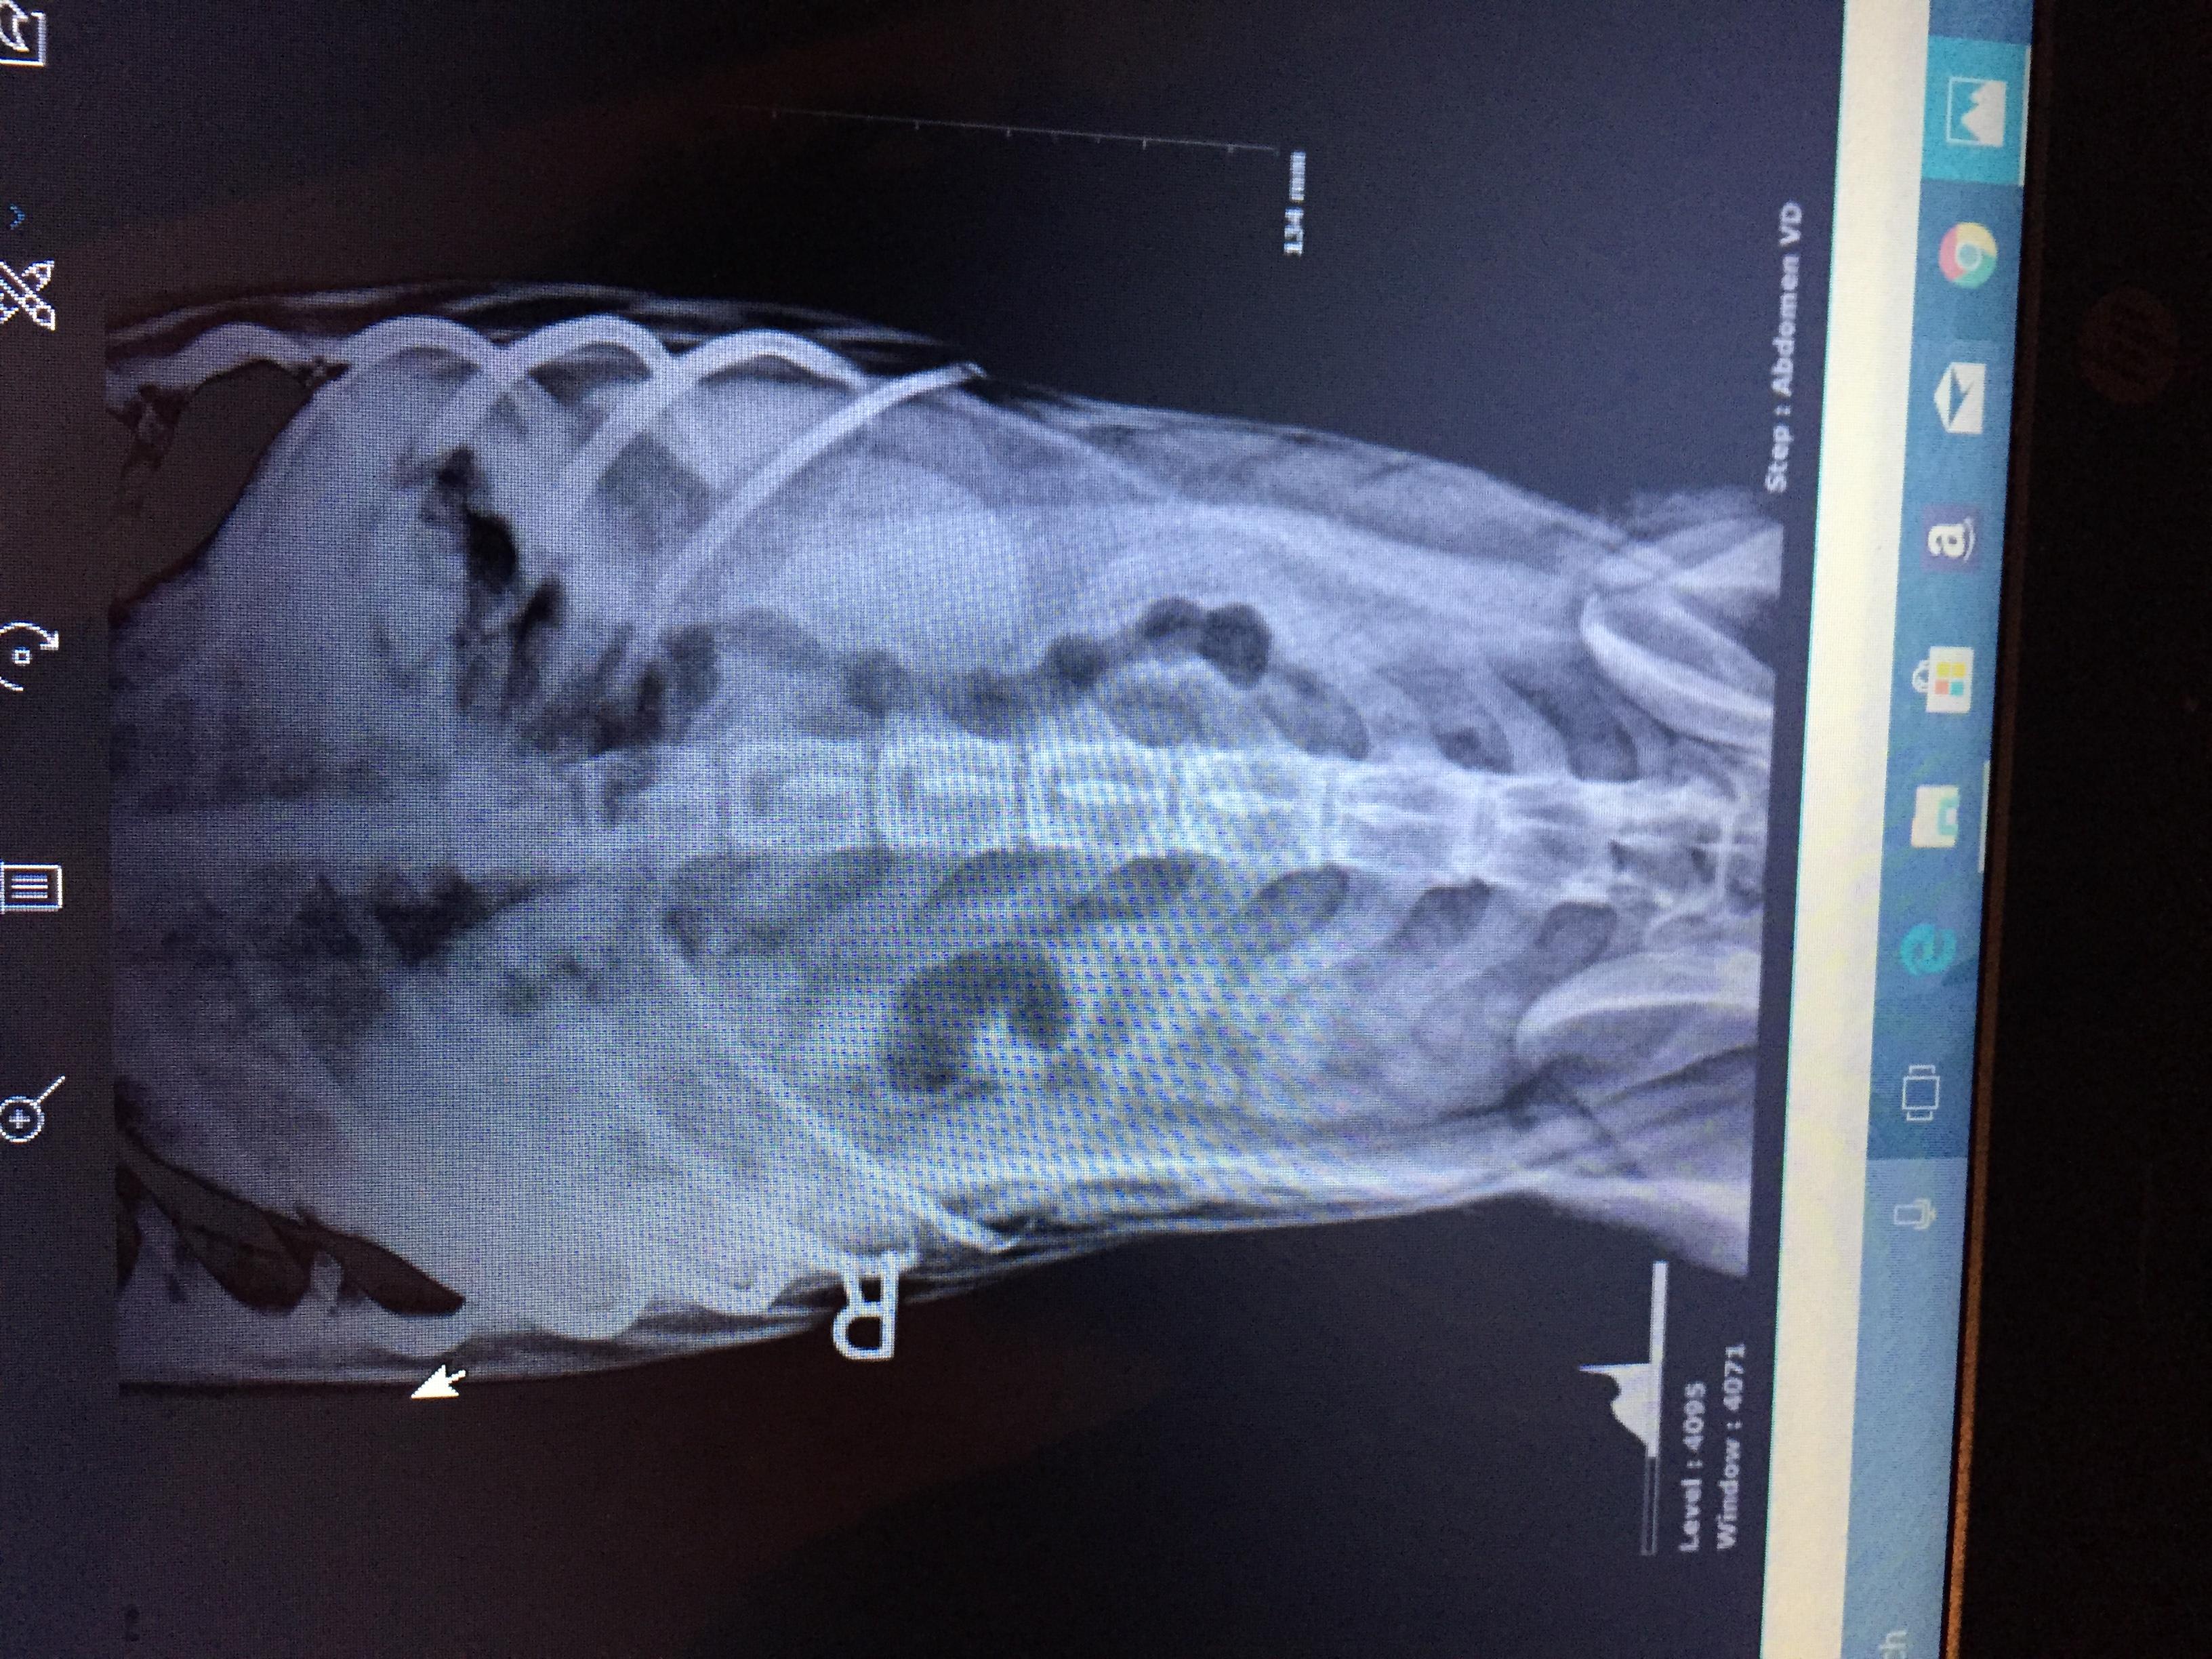

My was recently diagnosed with intestinal parasites called hook worm. the vets also did an X-ray and showed a little concern to a small area where her intestines look bunched up, they asked if she swallows things and I said she likes to eat her toys but always poops them out and I make sure of that. They didn't know what could be causing what they saw on the X-ray since it wasn't really big or obvious, my question is if these intestine parasites can do that to the intestines?

Typically, no, hookworms will not cause the intensities to become bunched. There are some parasites, specifically whipworms, that can cause an intusseception (where the bowel folds in on itself) but this usually causes severe illness (vomiting and diarrhea). Based on the X-rays, it does not look like your dog has any sort of intestinal blockage. If your dog is vomiting or having diarrhea for more than 24-48 hours after being treated for worms, then she will need to be checked out again by your vet. I hope this helps. Thanks for using Petco Pet Education Center, formerly Petcoach. Best of luck!